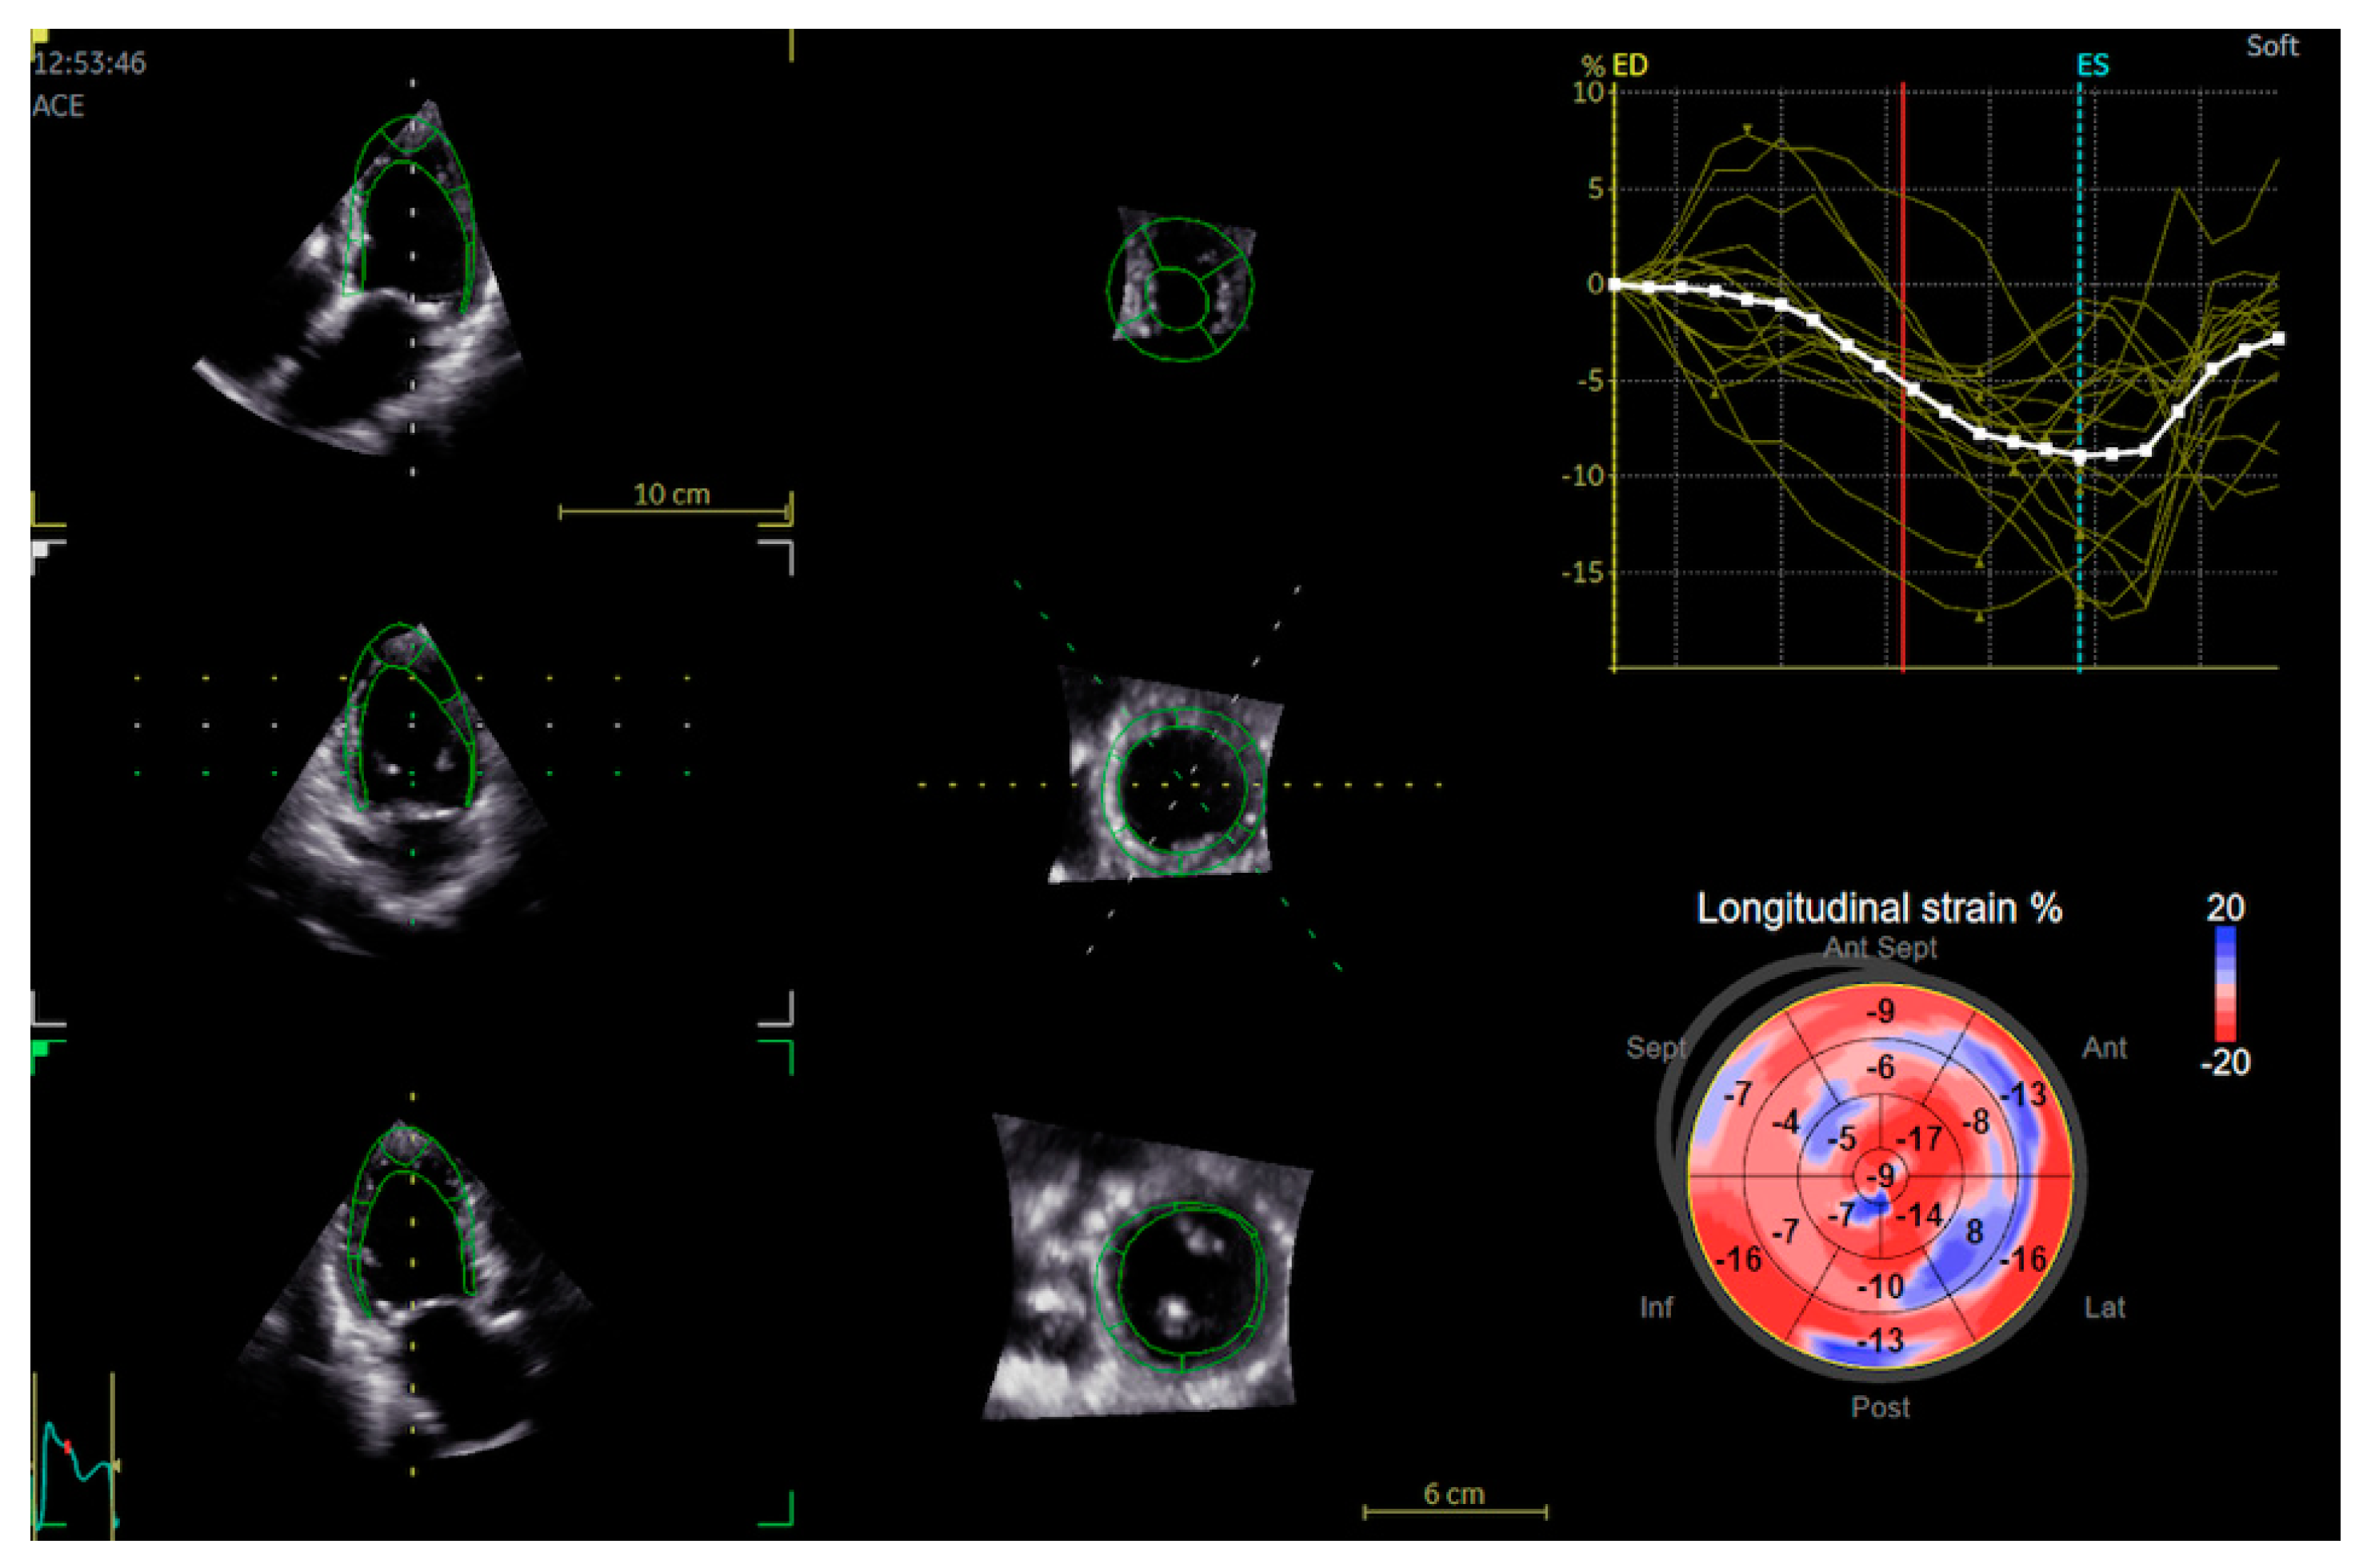

2.2. Echocardiography